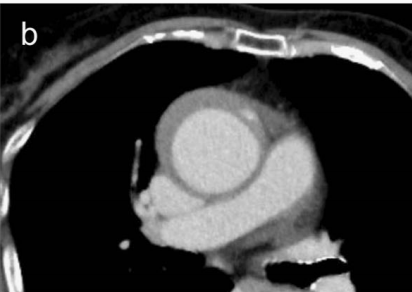

查到一篇文献,作者虽然用箭头标记了,并且是增强CT,但是鲁迅说:我大约肯定没有看出来,这是主动脉夹层!

图21